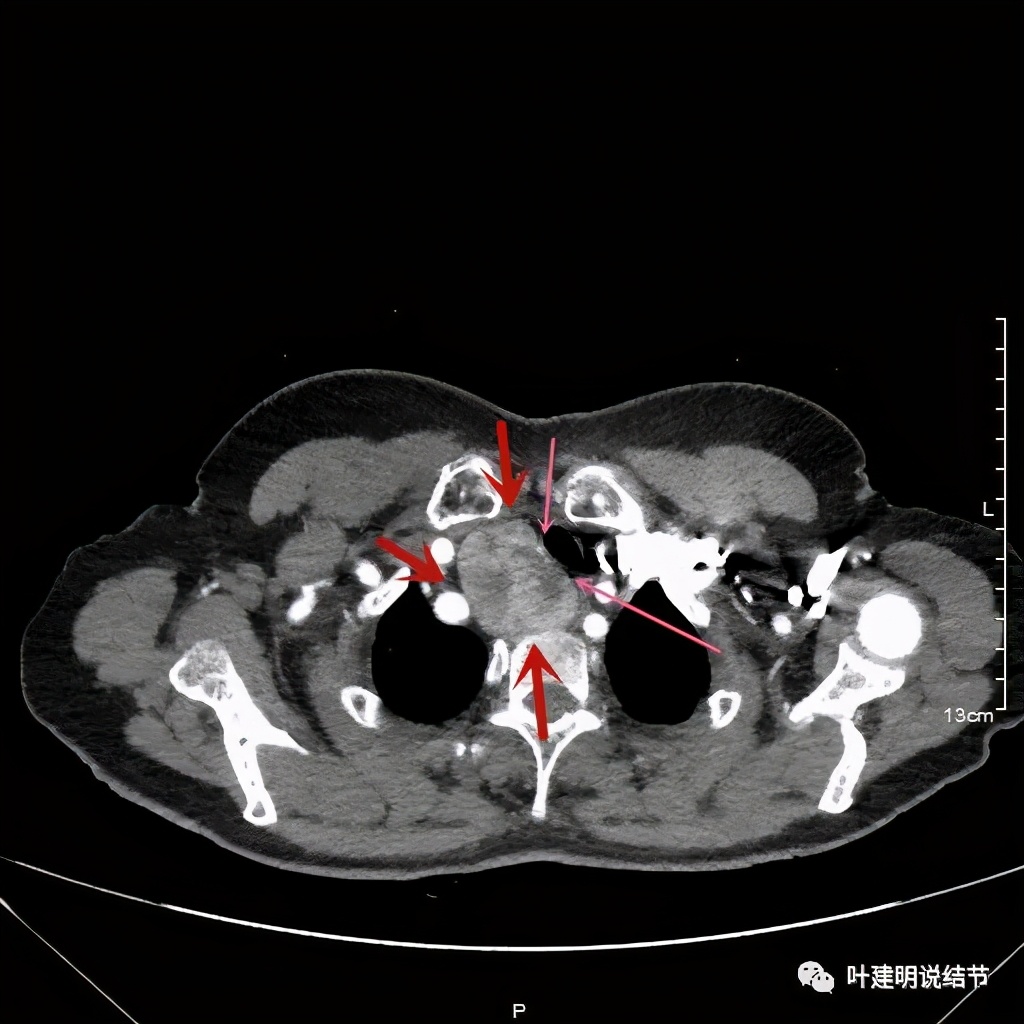

上图红色示肿瘤,黄色示气管,粉色示肿瘤与气管关系密切,而且肿瘤密度不均杂乱

上图红色示肿瘤,黄色示气管,而且肿瘤密度不均杂乱